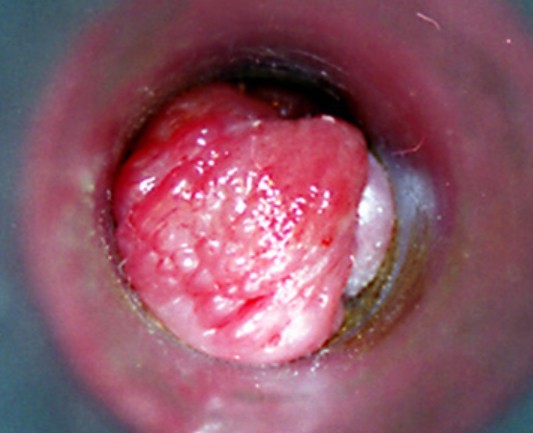

血栓性外痔

血栓性外痔

血栓性外痔

血栓性外痔

血栓性外痔

A:痔瘡是常見的肛周疾病,它是由直腸下段或肛管周圍的黏膜曲張靜脈造成。根據解剖位置的不同,齒狀線以上稱之為內痔,齒狀線以下稱之為外痔。外痔在臨床上大致可分為血栓性外痔、血管源性外痔、炎性外痔,以及結締組織性外痔。血栓性外痔大多是在外痔的血管團……

A:外痔的發生原因是由於長時間的便秘或者反覆的腹壓增高,影響到了肛周靜脈血液迴流,而隨著病情的演變會導致局部形成曲張的靜脈團,而在勞累之後或者暴飲暴食之後,會誘發急性血栓形成,所以就會表現為肛周的暗紫色的腫物,急性血栓性外痔經過有效的治療萎縮之……